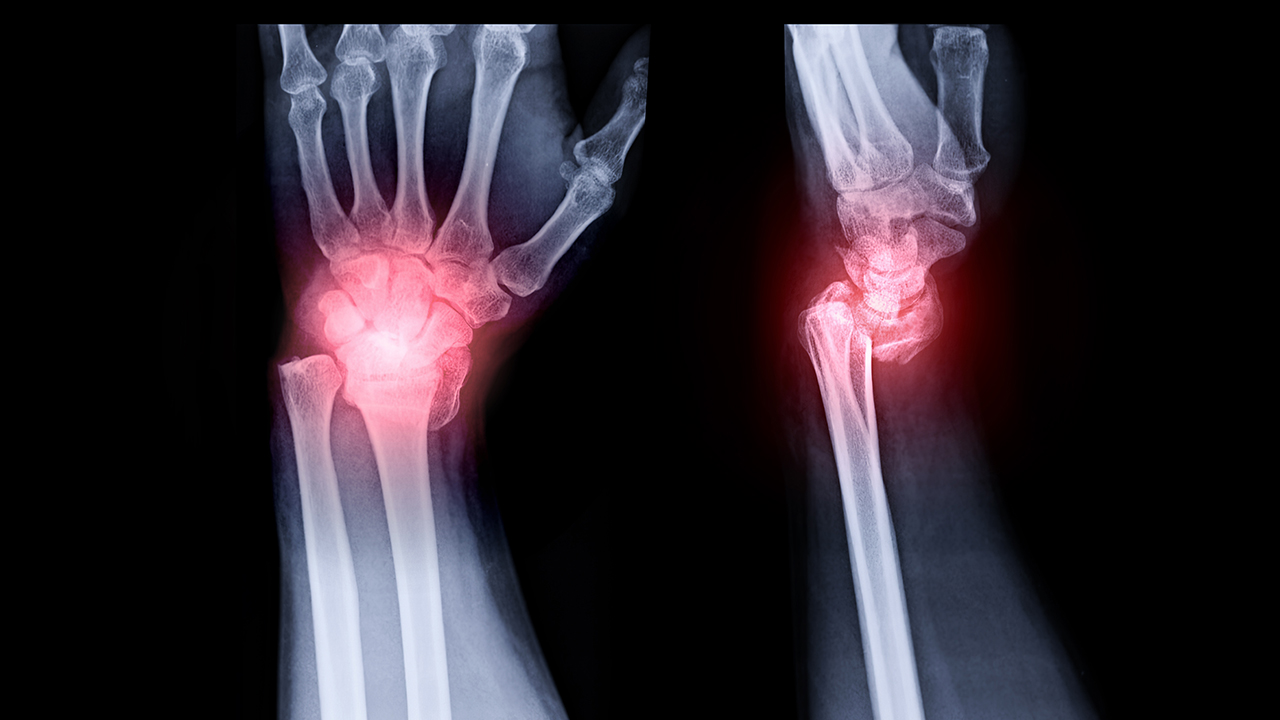

4、其他:除上述症状外,骨髓增生异常综合征还会出现不同程度的骨痛症状,多见于背部,多持续且逐渐加重,严重者可出现病理性骨折。患者还可出现肝脾肿大,可伴有脾功能亢进、腹水、食管胃底静脉曲张等症状。